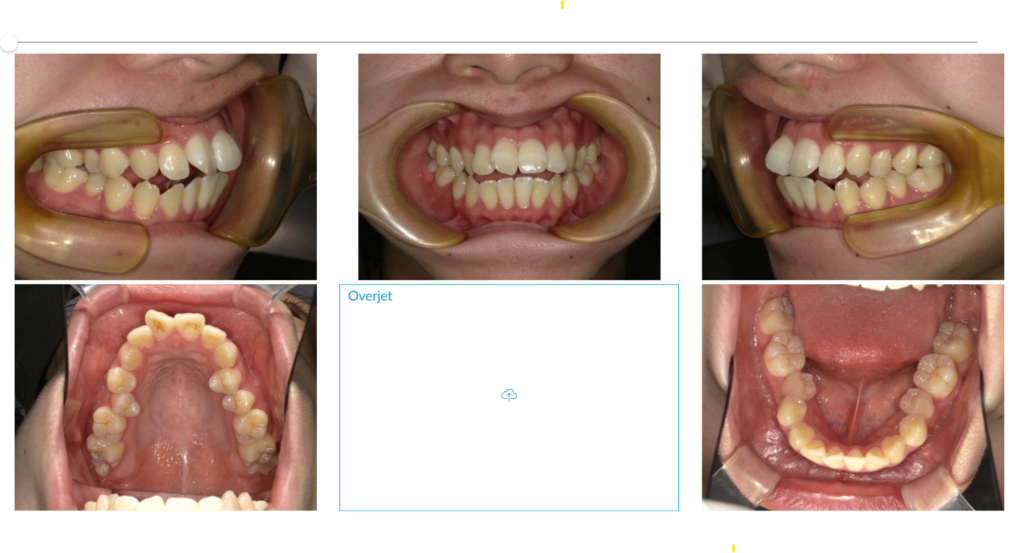

■ 治療前の状態【before】

上下の前歯の間に開咬が見られました。

口元の突出感があり、口を閉じると顎に力が入ってしまう状態でした。

■ 治療後の変化【after】

- 前歯の開咬が完全に改善し、しっかりと咬合できる状態に

- 顔貌の印象も柔らかくなり、横顔のラインが整った

- 機能的にも審美的にも大きな改善を確認